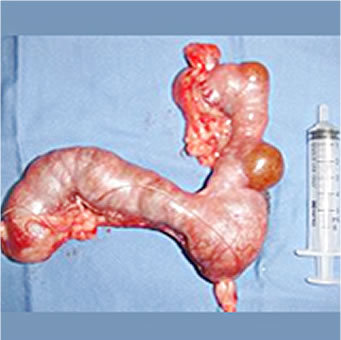

7才マルチーズ

子宮蓄膿症の摘出子宮。子宮嚢腫は、一部子宮壁が脆弱化し破裂寸前でした。